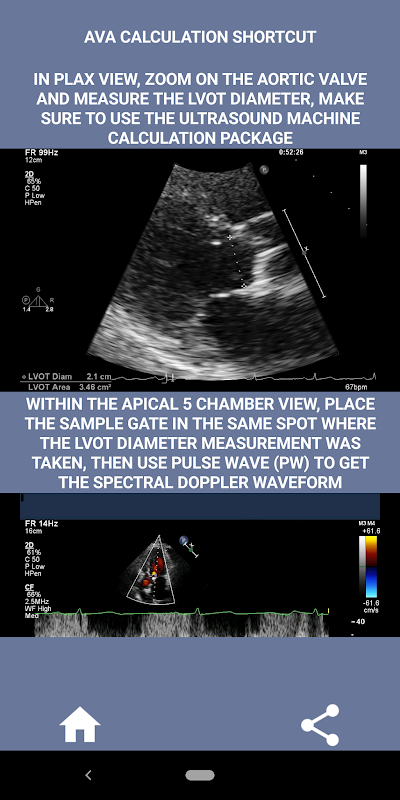

میری رائے میں ، اگر کوئی انٹرویو لینے والا اس مہارت کا مضبوطی سے مظاہرہ کر سکتا ہے تو اس شخص کو دوسرے درخواست گزاروں کے مقابلے میں بہت زیادہ فائدہ ہوتا ہے جو اس علاقے میں کمزور ہیں (یہ صرف منطقی ہے کیونکہ عام طور پر اتنے شہ رگ کے سٹینوس کیس ہوتے ہیں)۔ اگر آپ کارڈیک سونوگرافر کی پوزیشن کے لیے درخواست دے رہے ہیں ، کوئی ایسا شخص جس کو صرف اپنی مہارتوں کو تازہ کرنے کی ضرورت ہو ، یا ایکو اسٹوڈنٹ ، تو یہ ایپ آپ کے ذہن میں اس وقت ڈیزائن کی جانے والی کارڈیک سونوگرافر نے بنائی ہے۔ سادہ اور مختصر ، دائیں طرف بہت سی مثالوں والی ویڈیوز کے ساتھ اشارہ کرتا ہے کہ بالکل کہاں پیمائش کی جائے (مثال کے طور پر LVOT قطر) اور شائع شدہ ASE/ICAEL ہدایات کے مطابق پیمائش کیسے کی جائے۔